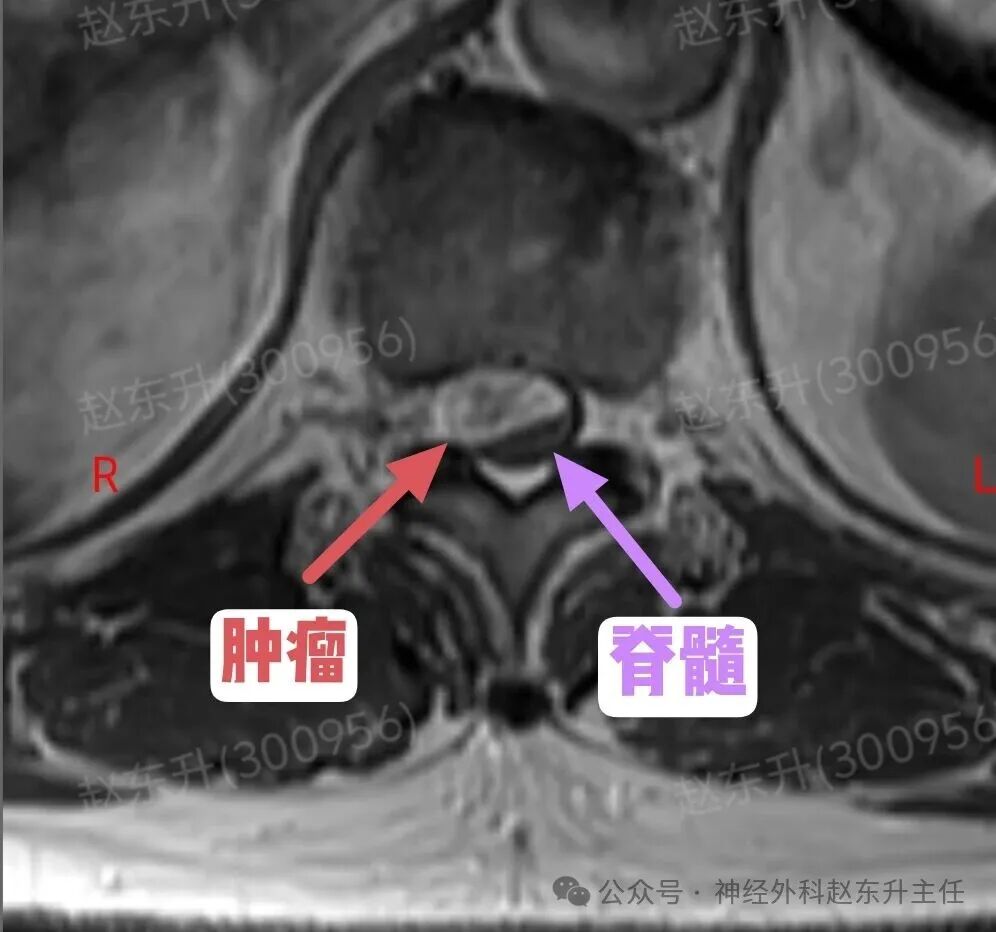

今天介绍一位58岁的男性患者,因为腰背部疼痛半年入院的。他半年前出现腰背部疼痛疼痛评分4-5分半双下肢乏力,但可独立行走。症状尚可忍受,但随后症状逐渐加重,疼痛有7-8分,吃药打针康复理疗。效果不明显,随后到医院查了一个磁共振,发现胸11-12水平椎管内巨大的肿瘤,肿瘤长在脊髓腹侧,外院的医生看了之后认为手术风险太大,不敢做,随后他来到西安市红会医院神经外科找到赵主任。入院后完善术前检查。随后在全麻下进行了肿瘤全切术中使用显微镜并进行术中电生理监测尽最大可能的保护脊髓神经,最终肿瘤予以全切,术后神经没有损伤,下肢可以正常下地活动大小便也正常,患者顺利出院了。

症状早期症状不典型:可能仅表现为相应神经根支配区的疼痛或感觉异常脊髓压迫症状:随着肿瘤增大,从前方直接压迫脊髓,可导致:运动功能障碍为主:由于压迫脊髓前角和皮质脊髓束(运动传导通路),常早期出现肢体无力、僵硬、肌肉萎缩,且可能比感觉障碍更早、更明显。感觉障碍:表现为受压平面以下的痛温觉减退(因压迫脊髓丘脑束)。括约肌功能障碍:大小便困难,出现较晚。不对称症状:由于肿瘤偏于一侧,症状常从一侧开始。影像诊断(MRI是金标准)位置:明确显示肿瘤位于椎管内、脊髓的正前方或前外侧形态与信号:常呈“哑铃形”,部分肿瘤通过椎间孔向椎管外生长。T1加权像呈等或稍低信号,T2加权像呈高信号,增强后显著不均匀强化关键观察点:放射科和外科医生会重点关注肿瘤与脊髓前动脉、椎动脉(颈段)的关系,以及脊髓受压移位的程度。